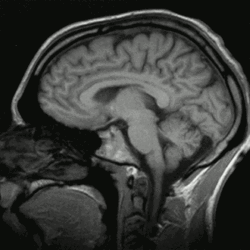

Einzelbild einer Magnetresonanz- tomographie eines menschlichen Gehirns; animierte Version mehrerer transversaler Schnittebenen -

Schnitt durch den Kopf eines Menschen, die Nase befindet sich links; animierte Version mehrerer sagittaler Schnittebenen -